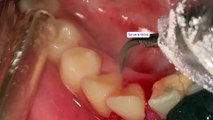

Can You Watch Till the End? Top 3 Most Shocking Tartar Removals!